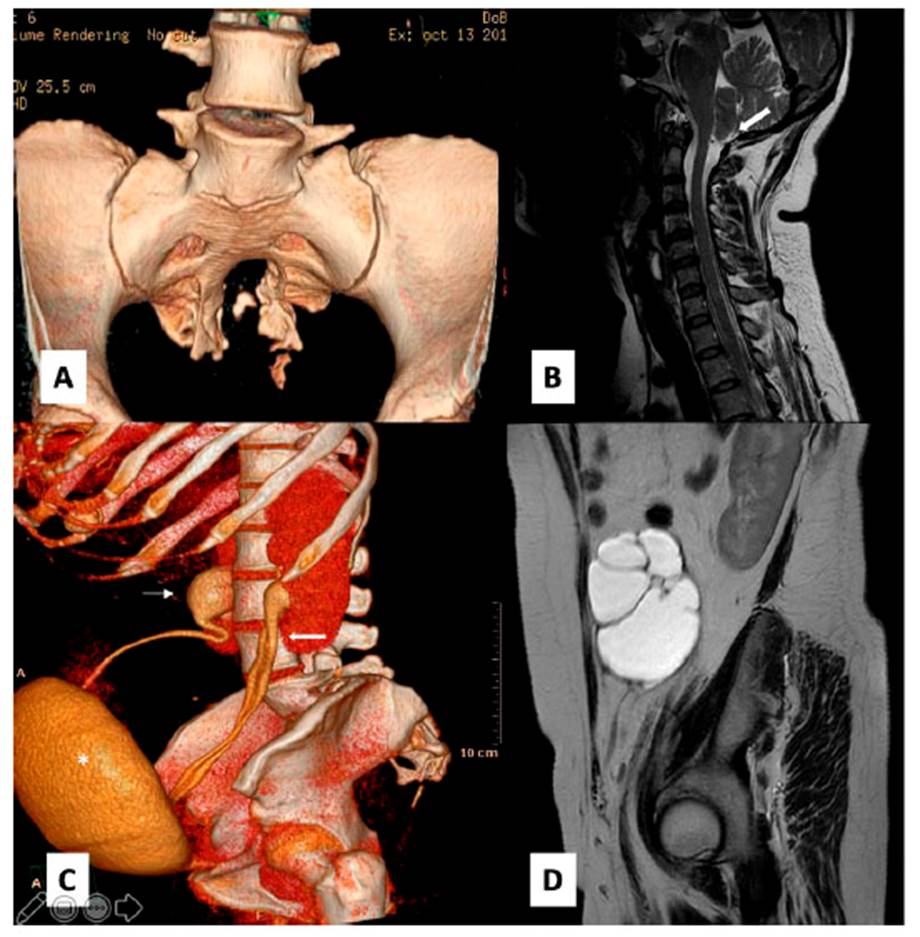

Paciente mujer de 42 años de edad, nuligesta y con antecedentes de quiste de ovario desde los 25 años, infección urinaria recurrente y síndrome ansiodepresivo. Se presenta en nuestro hospital con el síntoma principal de distensión abdominal e incomodidad en miembros inferiores sin un territorio radicular definido, cursa con estreñimiento crónico de 15 años de evolución y cefalea a las maniobras de Valsalva. El examen físico no mostró alteración neurológica, pero sí hemiabdomen inferior con gran distensión y cierta resistencia a la palpación. Los exámenes de imágenes mostraron evidencia de MSA, disgenesia sacra, masa quística ovárica izquierda, médula anclada, malformación de Chiari y doble uréter izquierdo (Figura 1 y Figura 2), sin alteraciones anatómicas digestivas y con la función renal normal, por lo que se diagnóstica MSA gigante tipo I de Cheng y síndrome de Currarino incompleto.

Figura 1 Resonancia magnética (RM) lumbosacra. 1A imagen sagital T1: proceso expansivo hipointenso en cavidad pélvica. 1B Imagen sagital T2: quiste que depende de saco dural a través de un defecto a nivel de S3 de 172 x 152 x 129 mm, también se muestra médula anclada (flecha). 1C Imagen axial T2 a nivel de S3

Figura 2 Lesiones asociadas. 2A Tomografía computarizada (TC) reconstrucción 3D que muestra el "sacro en cimitarra". 2B RM en T2: descenso de las amígdalas cerebelosas al límite, 1 cm por debajo de agujero occipital. 2C Urotomografía: vejiga desplazada y aplanada hacia anterior (*), doble uréter izquierdo (flecha gruesa) e hidronefrosis derecha (flecha delgada). 2D RM en T2: quiste anexial izquierdo

El diagnóstico se realiza con la tomografía computarizada (que proporciona detalles óseos) y la resonancia magnética (RM), que es la prueba de elección 9 (Figura 1). En la radiografía simple, el "sacro en cimitarra", que se observa en el 50 % de los casos, es el hallazgo patognomónico del MSA 7. El diagnóstico diferencial incluye las lesiones quísticas localizadas en la región presacra 9, tumores del tracto gastrointestinal o genitourinario, quistes epidermoides o dermoides, quiste óseo aneurismático, hamartoma, quiste hidatídico, lipoma, linfangioma, quiste perineural, quiste de duplicación rectal, tumores ginecológicos, teratoma o teratocarcinoma. Lo más importante para establecer el diagnóstico definitivo es detectar la comunicación entre la lesión quística y el espacio subaracnoideo, que puede, incluso, requerir de una mielografía.